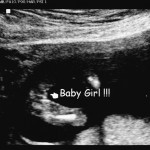

Categories events It’s a Girl! 16 Week Ultrasounds Post author By sean Post date September 7, 2012 Second set of ultrasounds, to help narrow the due date. At an estimated 16 weeks, we now know we are going to have a girl! Tags girl, ultrasounds